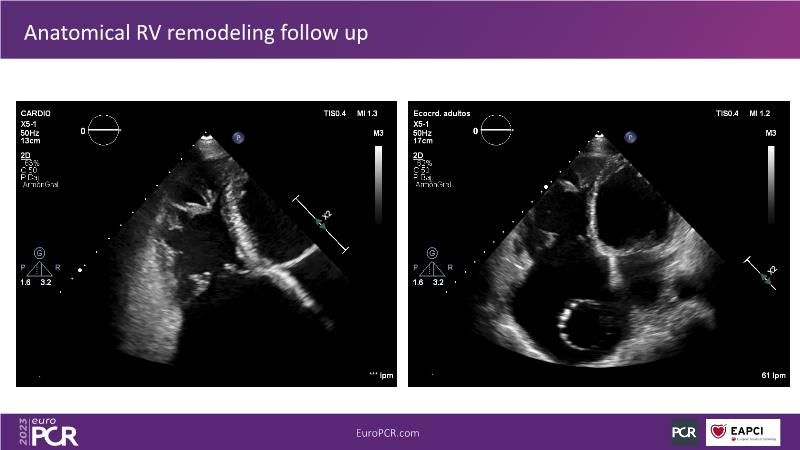

Discover the comprehensive guide to heterotopic valve replacement for patients experiencing right heart failure and tricuspid regurgitation. Join this session to gain insights into patient selection criteria, delve into the concept behind this innovative procedure, and grasp the fundamental aspects of its execution.